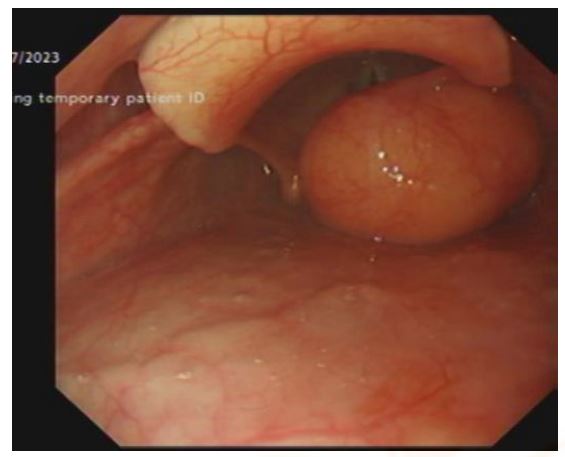

In July 2023, a 59-year-old female patient was referred to the Gastroenterology Department through the two-week-wait upper gastrointestinal (GI) pathway due to a history of progressive foreign body sensation and constant throat clearing. Notably, the patient did not report any voice changes, shortness of breath or weight loss. An oesophagogastroduodenoscopy revealed a large and smooth submucosal mass in the right supraglottic region (see Figure 1A), with the rest of the endoscopic examination being unremarkable. Subsequently, the patient was referred to the Ear, Nose and Throat (ENT) Department on a two-week-wait pathway in order to conduct further investigations of this mass.